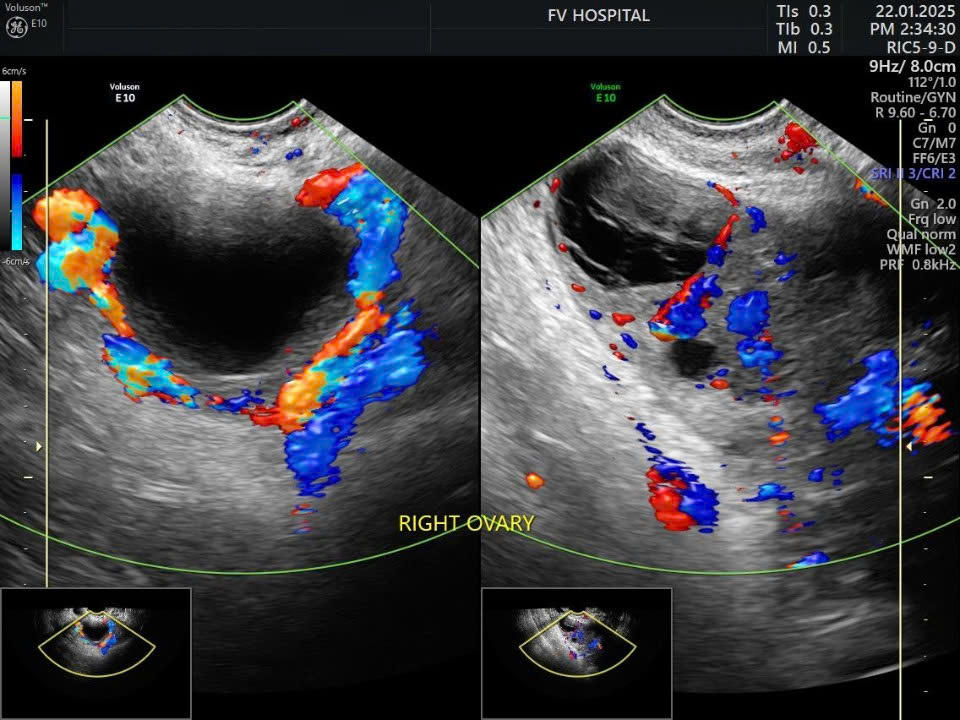

Chị X.A., 30 tuổi, đến Bệnh viện FV với triệu chứng đau nhẹ vùng hố chậu phải. Sau 24 giờ, cơn đau tăng đột ngột, kèm buồn nôn, nôn ói. Siêu âm cho thấy buồng trứng phải phình to gần gấp đôi.

Hình siêu âm tái khám sau 1 tuần: bên trái buồng trứng xoắn, bên phải buồng trứng đã được tưới máu lại bình thường sau phẫu thuật - Ảnh: FV